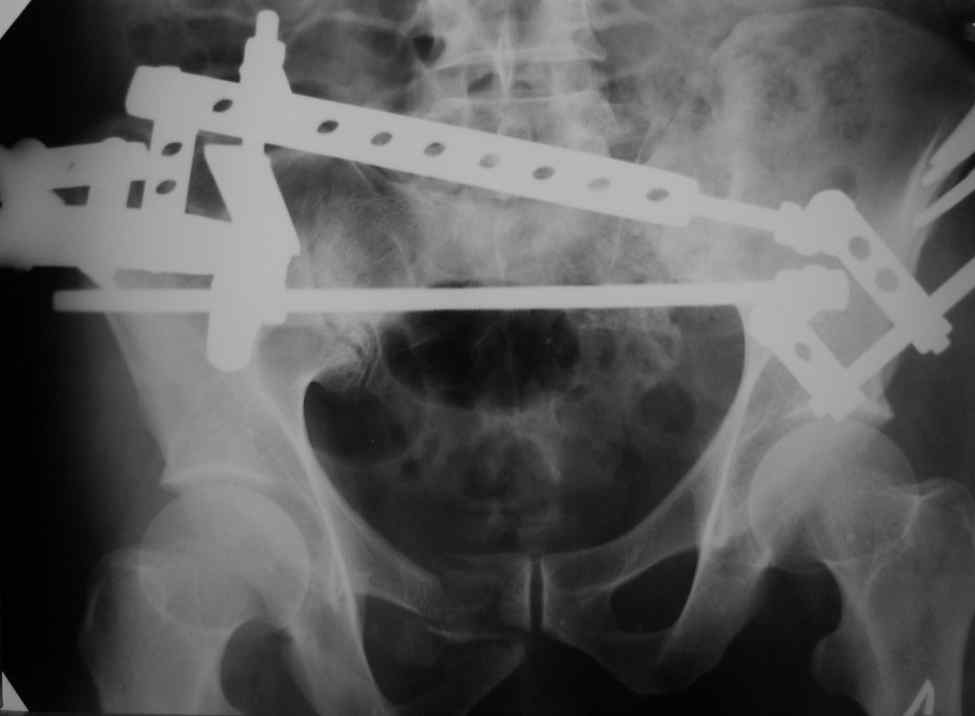

Можно посмотреть на нынешние снимки таза в аппарате, фас и inlet?

Снимки вот